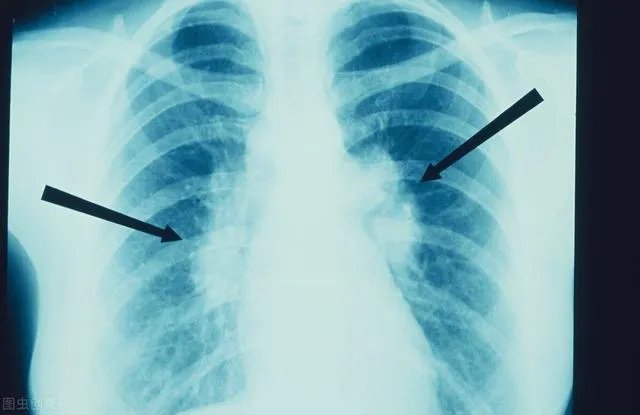

在了解肺结节之前,先给大家科普一下肺结节的定义,在医学上,我们一般将在肺部X光片或者CT检查中,直径小于3cm的高于正常肺组织的异常密度影,称之为肺结节,它的形态一般呈圆形或者类圆形,密度可以是稍高于肺组织,也可以明显高于肺组织。

根据密度的差异,肺结节又可以分为三大类型:磨玻璃结节、亚实性结节和实性结节。